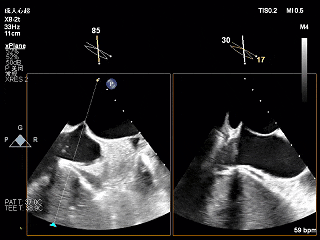

术前X-Plane

全麻下穿刺右股静脉,在TEE指导下完成房间隔穿刺,穿刺处与二尖瓣瓣环距离3.85cm。将superstiff导丝送至左房,应用18F鞘管扩张穿刺部位,沿导丝将可操控导引导管送入左肺静脉。